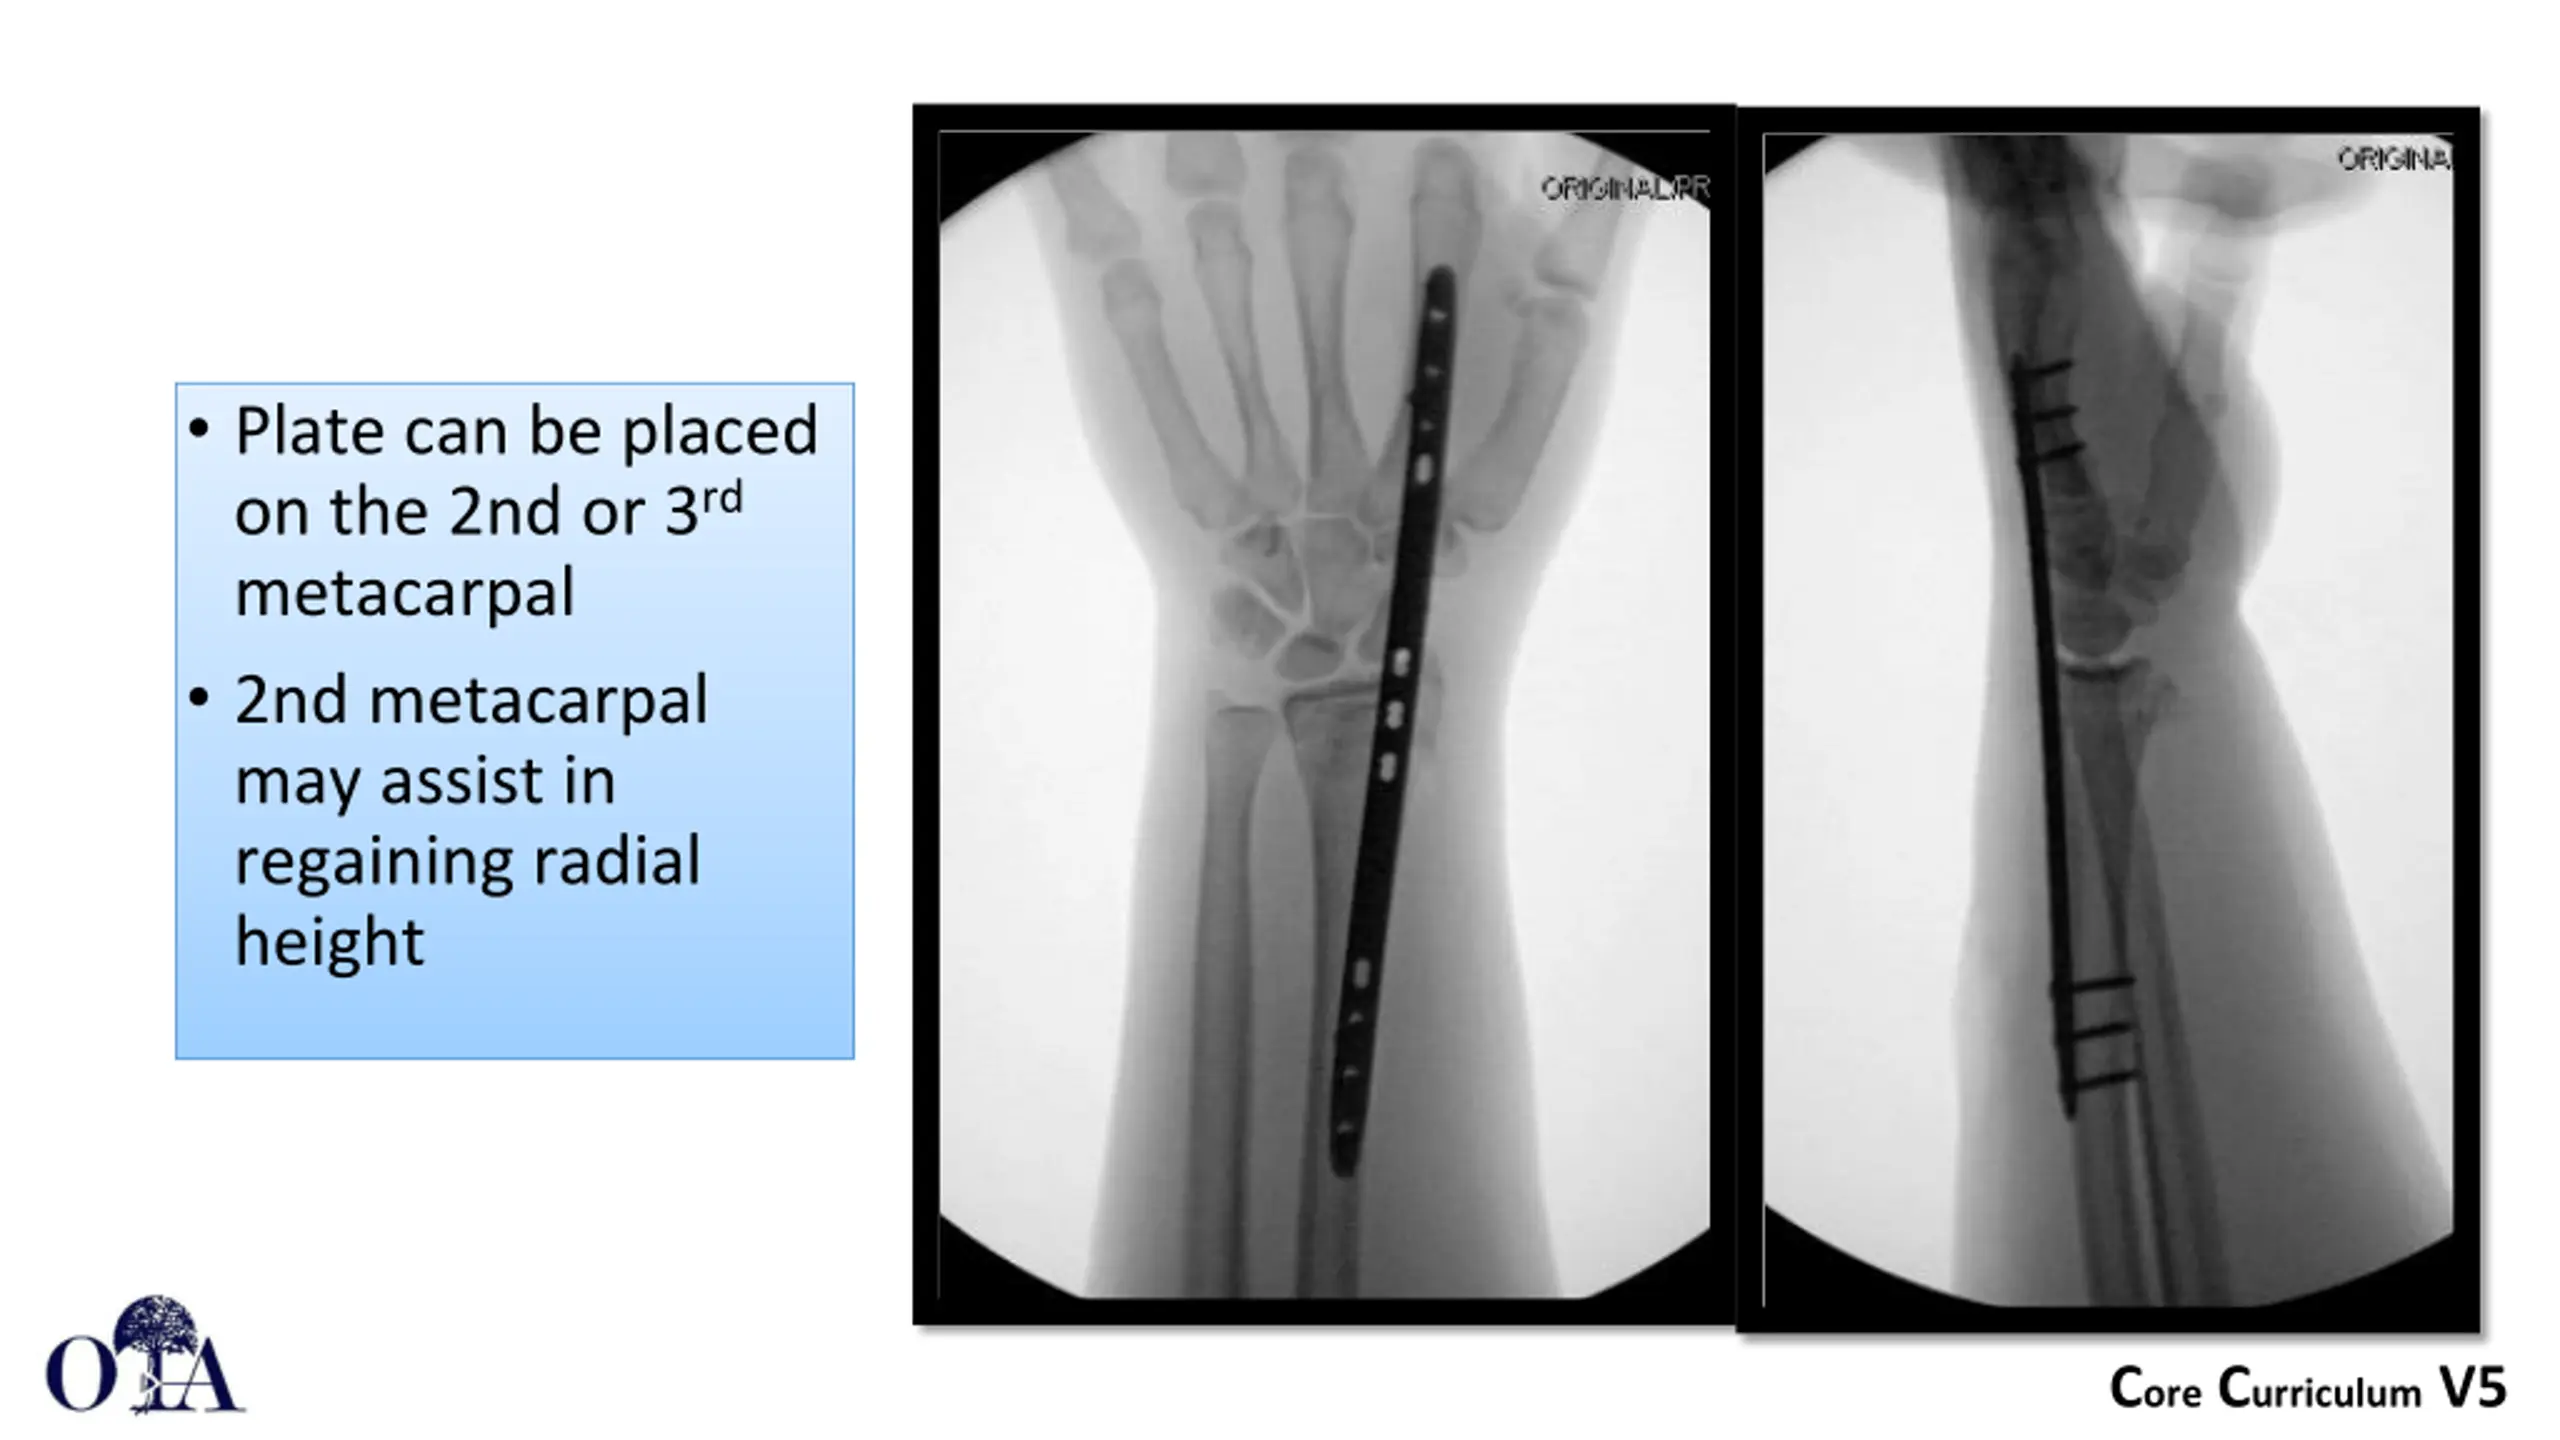

Distal Radius: Dorsal Spanning Plate Limited Incision localized fluoroscopically Centered between 2ndand 3rd metacarpal Dorsal aspect of the radius Deep exposure between 2nd and 3rdcompartments Superficial Radial Nerve at risk Plate slid under the extensor retinaculum which is never exposed Image courtesy of G. Moloney Core Curriculum V5

Plate can be placed on the 2nd or 3rd metacarpal 2nd metacarpal may assist in regaining radial height Core Curriculum V5

Plate can be attached to the metacarpal first and then used to regain length Core Curriculum V5